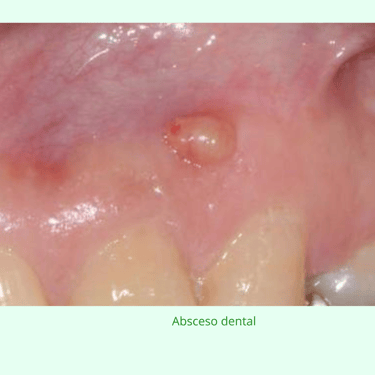

Las lesiones periapicales son infecciones crónicas que se desarrollan alrededor de la raíz del diente, generalmente debido a una infección no tratada en la pulpa dental. Se manifiestan como dolor, hinchazón o un absceso.

Importancia: Las lesiones periapicales, como abscesos y granulomas, se forman en el extremo de la raíz del diente. Tratarlas a tiempo es crucial para prevenir la propagación de la infección y la pérdida del diente.